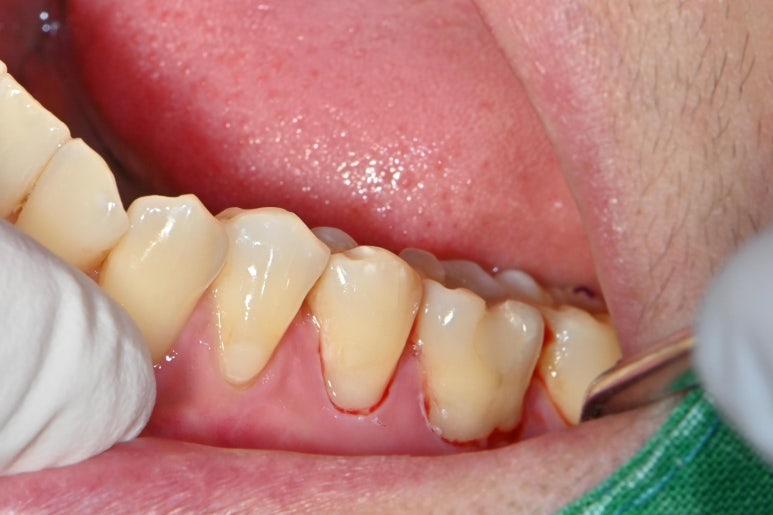

먼저 치아 표면을 깨끗하게 정리합니다.

스케일러나 표면 연마제등을 이용하여

남은 치석이나 치태를 깨끗하게 정리합니다.

그후에 사진에 보이는 검정 실인 징지코드를 넣습니다.

징지코드는 잇몸 하방에서 올라오는 삼출물이나

혈액을 억제하는 효과가 있습니다.

그리고 혀 안쪽으로 솜을 넣어서

침이 넘어 오지 않게 철저하게 방습을 합니다.

그 후에 본드필을 붓으로 한땀한땀 떠서

치아에 올려서 중합시켜 줍니다.

레진과는 다르게 광중합제가 별로 안들어 있어서

완료후 5~10분정도 굳기를 기다려야 합니다.

다 굳은 후 과잉의 본드필을

물이 나오는 기구를 이용하여 제거해주고

실을 제거해주면 위의 사진처럼 마무리가 됩니다.